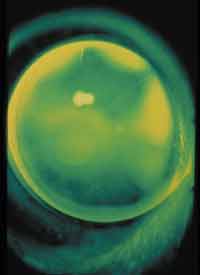

Figure 1. Reverse geometry RGP fitted on a post-PK cornea. |

Surgeries such as penetrating keratoplasty (PK), radial keratotomy (RK), photorefractive keratectomy (PRK) and LASIK may cause corneal distortion. Post-surgical corneal contour dictates the most appropriate lens design. For post-PK patients with raised or steep grafts, prescribe spherical or aspheric rigid lenses with large overall and optic zone diameters. For sunken or flat grafts, a reverse geometry lens design helps avoid excessive central clearance and optimize lens centration. Reverse geometry designs also benefit most post-RK patients. If corneal distortion results subsequent to PRK or LASIK, try spherical or aspheric rigid lens designs. Corneal topography is extremely helpful in fitting post-surgical corneas.